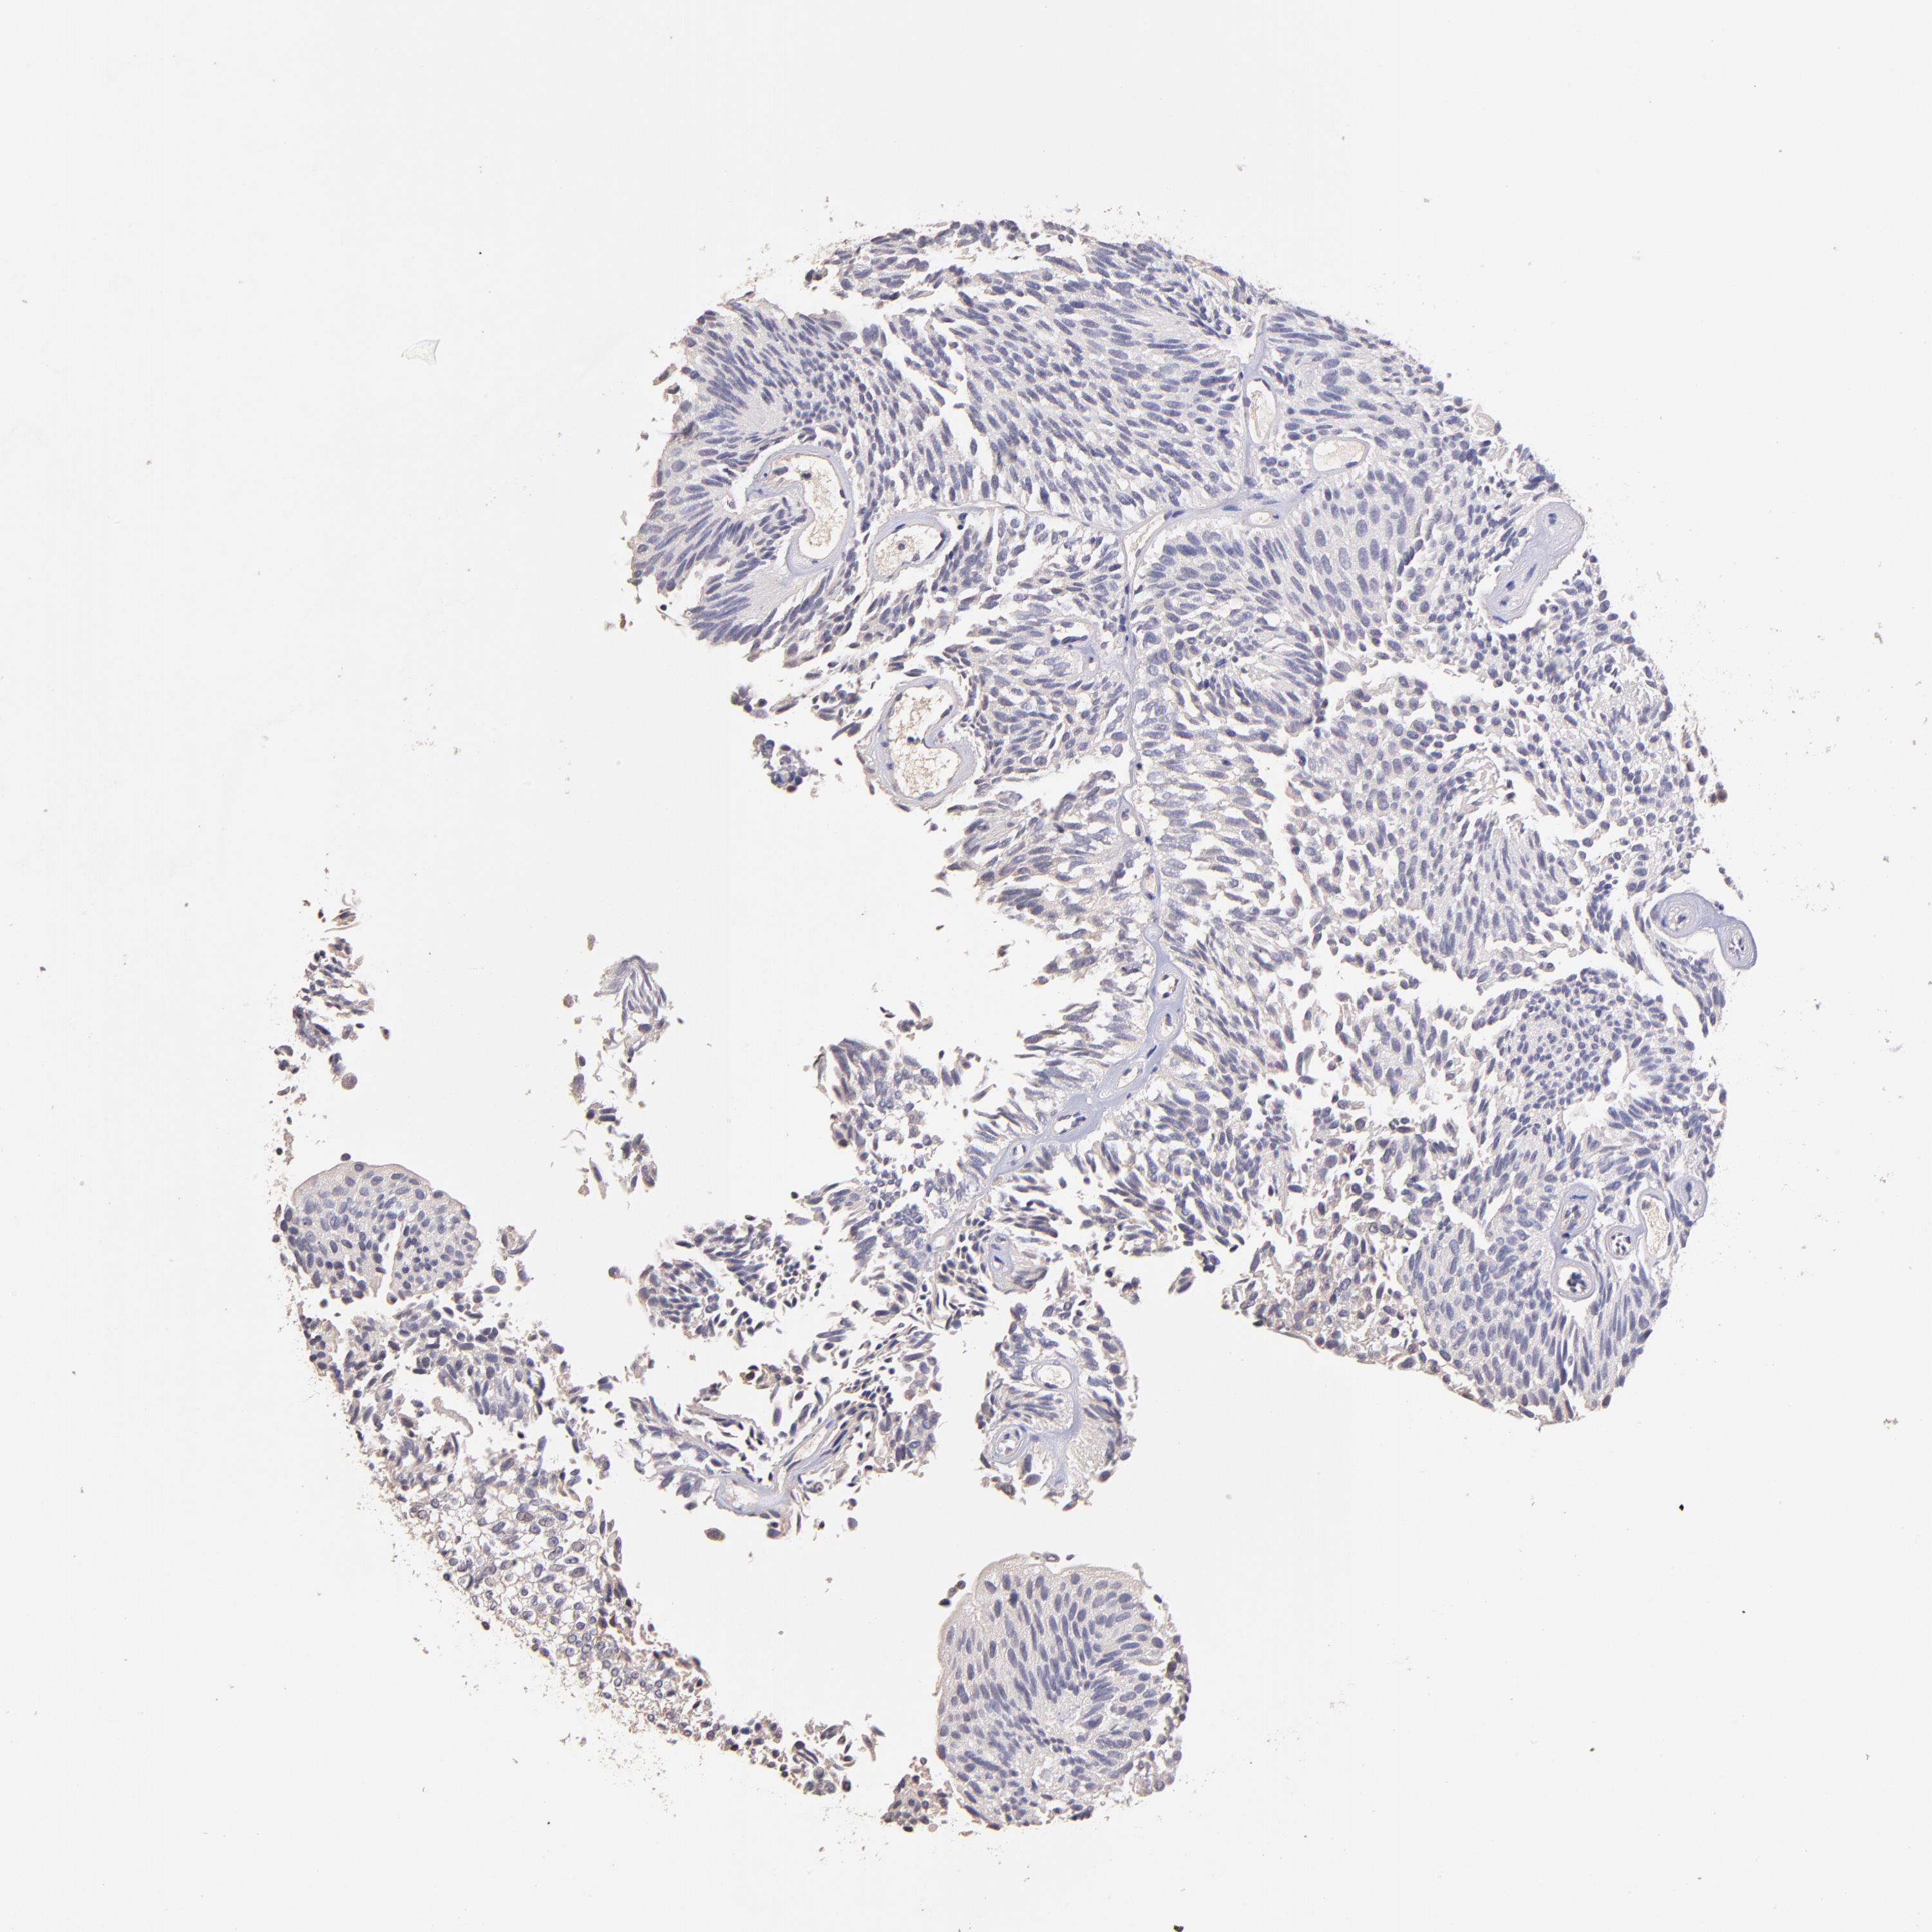

UROTHELIAL CANCER - Protein expressioni

A mouse-over function shows sample information and annotation data. Click on an image to view it in a full screen mode. Samples can be filtered based on level of antibody staining by selecting one or several of the following categories: high, medium, low and not detected. The assay and annotation is described here.

Note that samples used for immunohistochemistry by the Human Protein Atlas do not correspond to samples in the TCGA dataset.

Antibody stainingi

Antibody staining in the annotated cell types in the current human tissue is reported as not detected, low, medium, or high, based on conventional immunohistochemistry profiling in selected tissues. This score is based on the combination of the staining intensity and fraction of stained cells.

Each image is clickable and will lead to virtual microscopy that enables deeper exploration of all samples and also displays staining intensity scores, fraction scores and subcellular localization as well as patient and tissue information for each sample.

Antibody HPA002633

Antibody HPA046758

Antibody CAB010906

Staining

High

Medium

Low

Not detected

Intensity

Strong

Moderate

Weak

Negative

Quantity

>75%

75%-25%

<25%

None

Location

Nuclear

Cytoplasmic/membranous

Cytoplasmic/membranous,nuclear

Urothelial carcinoma, High grade

Urothelial carcinoma, Low grade